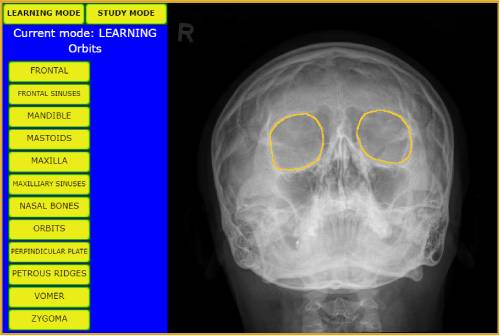

Learn bony anatomy from X-ray images - hover over the bones to display the names in learning mode, then test your knowledge and retention in study mode.